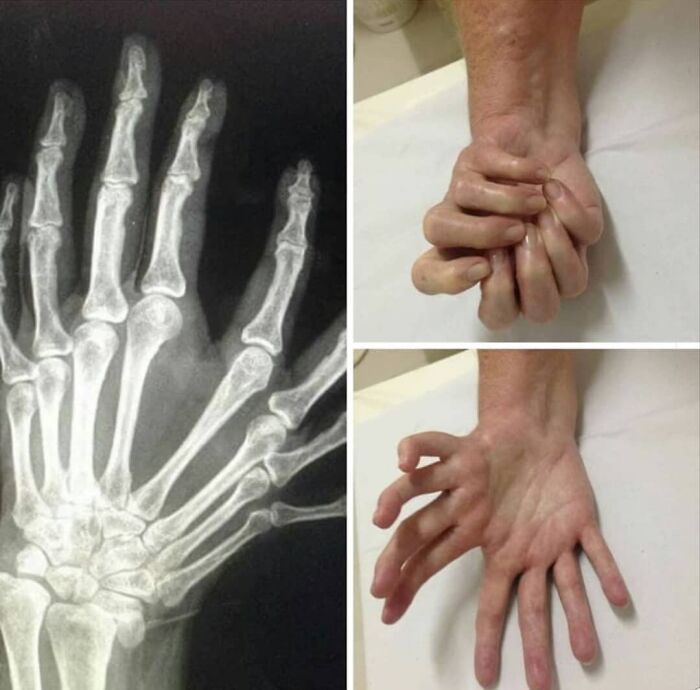

Ulnarna dimelia (tzw. „lustrzana ręka”) — brak kości promieniowej, podwojenie kości łokciowej i symetryczna polidaktylia

Ciekawy przypadek kciuka triphalangealnego

Kciuk triphalangealny (TPT) to wrodzona anomalia, w której kciuk ma dodatkową paliczkę. Często ma podłoże dziedziczne; może występować obustronnie lub jednostronnie. Kciuk bywa wydłużony, o wyglądzie zbliżonym do palca wskazującego. Kształt dodatkowej paliczki wpływa na obecność klinodaktylii, a elementy anatomiczne pierwszej promieniowej osi mogą być hipoplastyczne lub nieobecne, co daje różne stopnie sztywności lub niestabilności. Dziś chirurgiczne leczenie ma na celu poprawę funkcji i wyglądu kciuka.